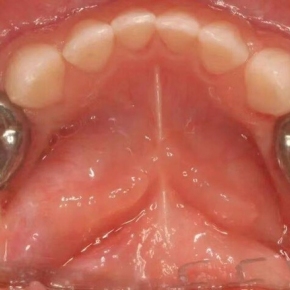

修复